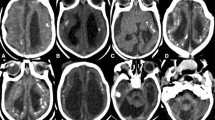

The reported risk of fetal/infant abnormalities with maternal ZIKV infection ranges between 1 and 29% [42]. The most prevalent brain congenital defects reported are the following: calcifications at the cortical-subcortical junction (Fig. 1a, b) (92.9%); basal ganglia calcification (Fig. 1c) (57%); periventricular calcifications (29.5%); ventriculomegaly (Fig. 1d, e, g, i, j, k, l) (63.1%); cerebellar abnormalities (Fig. 1d, j, k, l) (47.9%); corpus callosum abnormalities (Fig. 1d, g, h, l) (46.2%); and microcephaly (39.7%) (Fig. 1d), almost 100% when the infection occurs in the first trimester of pregnancy [43•].

Brain images of infants diagnosed with CZS. CT scan slices: images a, c, i, j, and k. MRI images: b, d, e, f, g, h, k, and l. a (CT) and b (MRI): coarse and punctate calcifications at the cortico-subcortical junction, predominating in the frontal lobes. c: basal ganglia calcifications. d: marked microcephaly with redundant scalp skin in the occipital region. e: marked dilatation of supratentorial ventricular system, simplified gyral pattern of the brain, and prominence of the subarachnoid space in the frontal regions. f: malformations of cortical development compatible with polymicrogyria in the frontal lobes with sparing of posterior cortical areas. g: thin/hypoplastic corpus callosum. h: short corpus callosum with dysgenetic aspect. i and j: tetraventricular dilatation, simplified gyral pattern of the brain, cerebellar and pons hypoplasia, and cortico-subcortical and periventricular calcifications. k: asymmetric cerebellar hypoplasia with greater involvement of the right hemisphere, marked dilatation of the lateral ventricles with thinning of cerebral mantle, and prominence of cisterna magna. l: severe cerebellar hypoplasia

Brain calcifications are common in CZS, occurring in 88–100% of patients [44], especially involving the gray-white matter junction (Fig. 1a, b) [45]. Calcifications were also identified in basal ganglia (Fig. 1c), thalamus, cortex, and periventricular regions. In patients with periventricular calcifications (Fig. 1i), these were associated with areas of parenchymal thinning [46•].

Cortical-subcortical calcifications were located mainly in the frontal (Fig. 1a, b) (100%) and parietal (68.7%) lobes, and less frequently in the occipital (50%) and temporal (43.7%) lobes. Brain calcifications described in CZS can also be punctate and coarse (Fig. 1a, b) [47]. In some cases, a layered calcification appearance can be seen in cortical gray and white matter [48•].

As consequence to microcephaly, redundant skin of the scalp has been described in 67.4% of infants. Redundant skin could be best demonstrated by manually creating folds in the scalp and is evident in the forehead (37.3%) or in the occipital and nuchal regions (Fig. 1d) (47%) [32]. Skin redundancy is best explained by the collapse of the skull, which previously had larger dimensions. The latter can be the result of the decreased brain size or the suppressed cranial osteogenesis caused by ZIKV [17, 44]. Periorbital fullness, epicanthal folds, and mild retrognathia are the main facial features of these infants [32].

Malformations of Cortical Development

Associated with the frequent finding of malformations of cortical development, infants with CZS have large reductions in parenchymal volume. In some cases, this is accompanied by enlargement of the subarachnoid spaces (Fig. 1e, i) [54,55,56,57]. Ventriculomegaly (Fig. 1d, e, g, i, j, k, l) occurs in 63% of patients with CZS [43•].

Corpus callosum abnormalities are a common finding in CZS and occur in about 46% of cases [43•]. Typically, there is a thin, hypoplastic (Fig. 1d, g, l), dysmorphic (Fig. 1h), or absent corpus callosum. Formation of the corpus callosum occurs between 8 and 20 weeks of gestational age [55, 58], suggesting that at least in some cases the insult to CNS morphology occurs concurrent with corpus callosum development.

Cerebellar and brainstem hypoplasia (Fig. 1d, j, k, l) were present, respectively in 24% and 20% of these infants [52, 61]. The cerebellar hemispheres usually had symmetric involvement, although asymmetric unilateral cerebellar hypoplasia (Fig. 1k) has been reported. The brainstem hypoplasia frequently involved the pons (Fig. 1d, g, j, l) [58••]. Brainstem and cerebellar calcifications occurred, respectively in 9.9% and 2.9% of infants [52, 61,62,63].